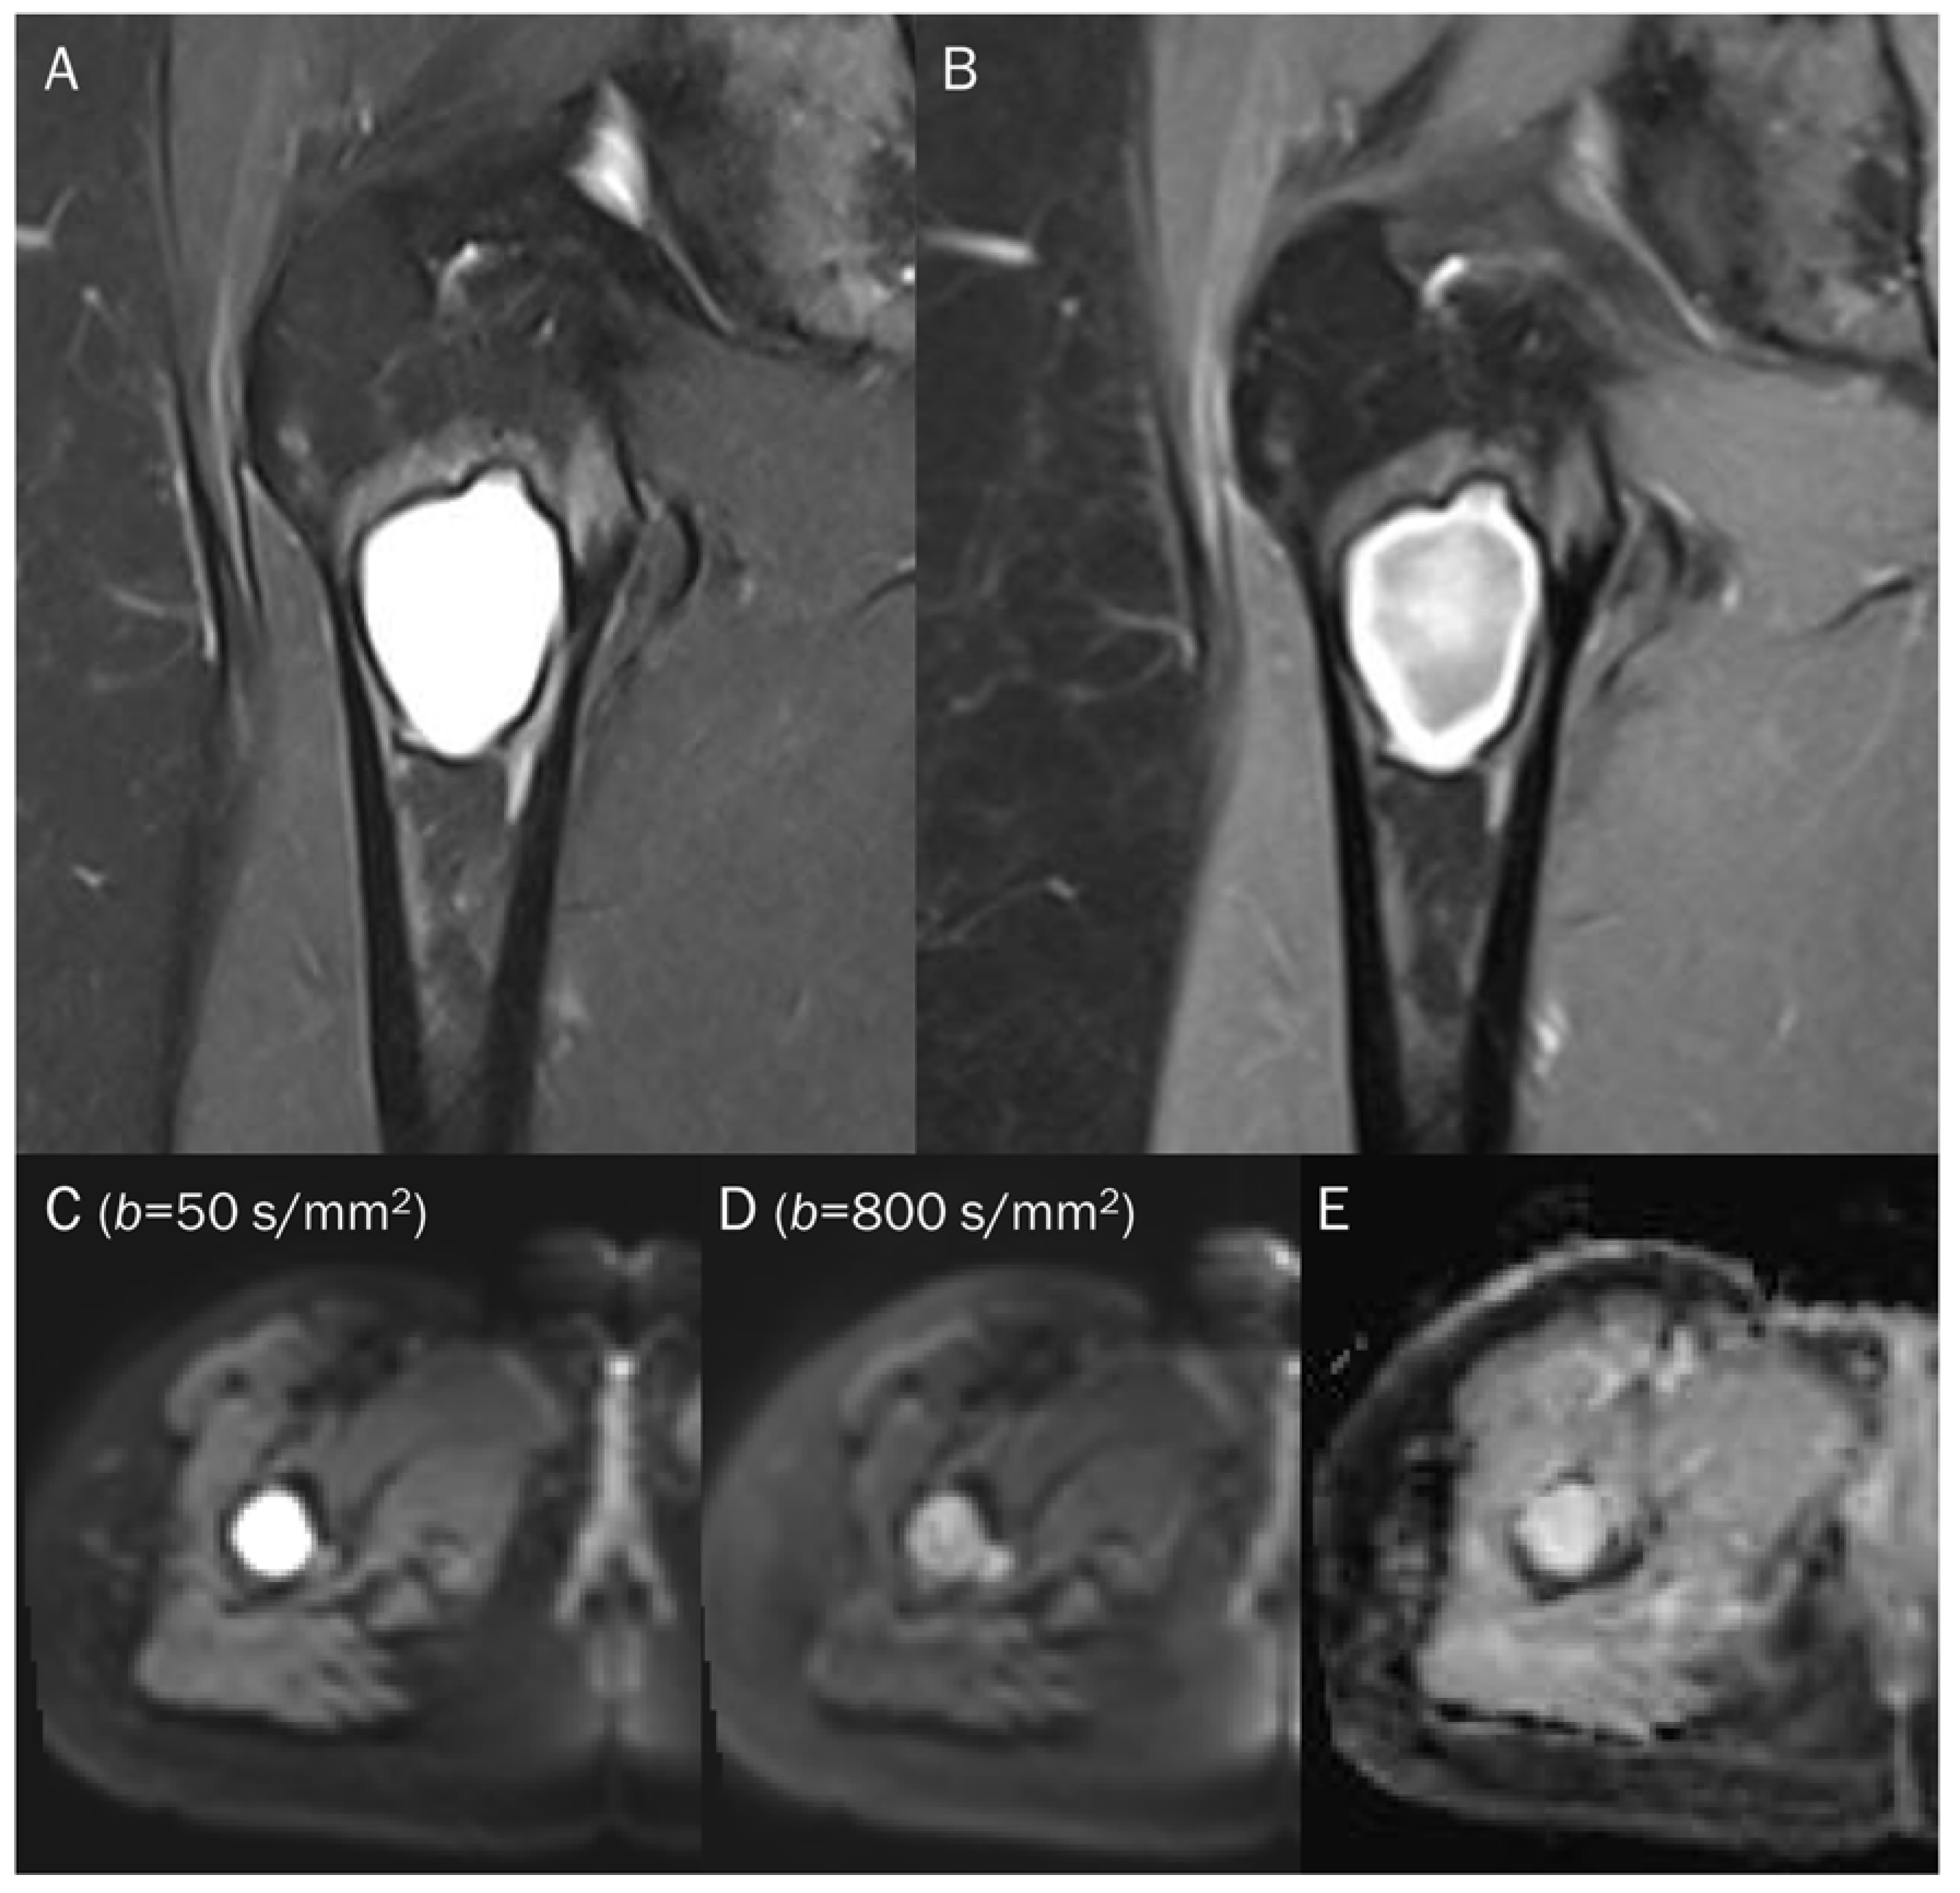

7.1. Cyst

- Subhawong, T.K.; Durand, D.J.; Thawait, G.K.; Jacobs, M.A.; Fayad, L.M. Characterization of soft tissue masses: Can quantitative diffusion weighted imaging reliably distinguish cysts from solid masses? Skelet. Radiol. 2013, 42, 1583–1592. [Google Scholar] [CrossRef]